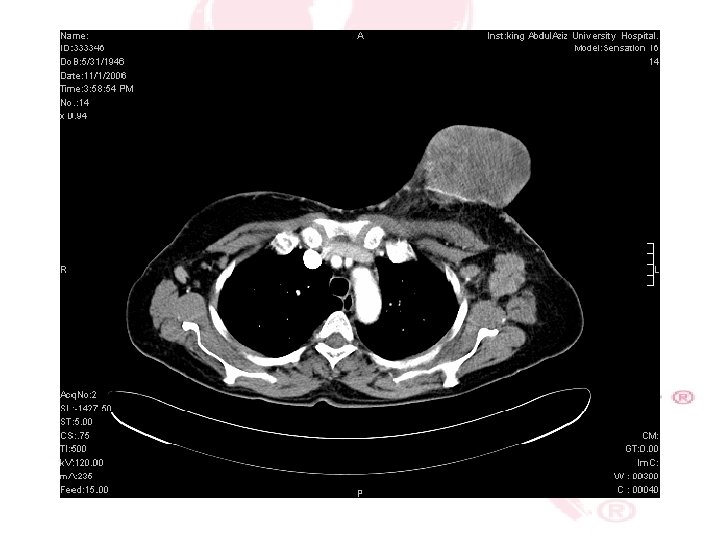

CT SCAN CHEST , ABDOMEN &PELVIS